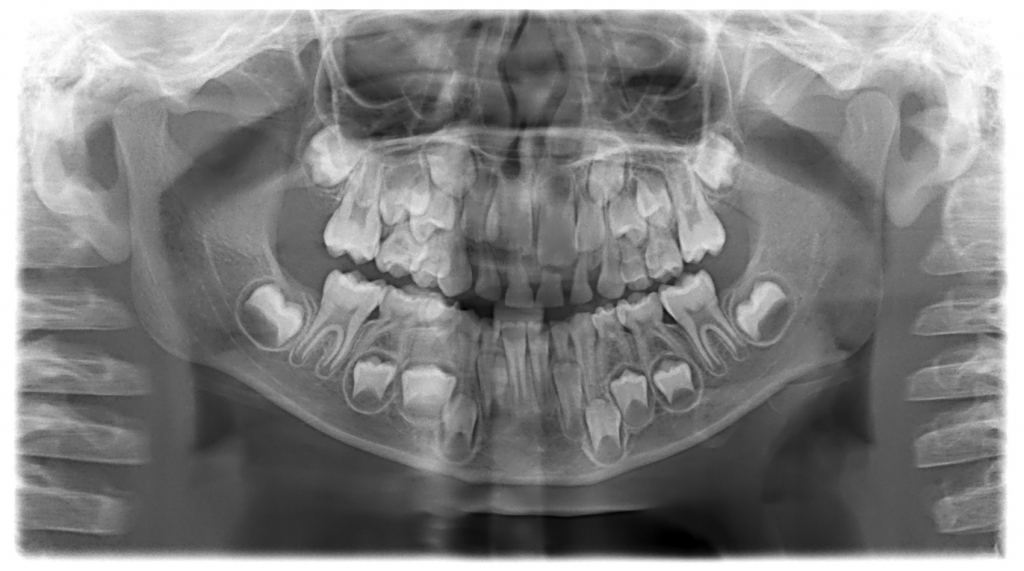

A kisgyerekek koponyája félelmetes

Nemcsak a cápának nőnek duplasorban a fogai, életünk során mi is átmegyünk egy ilyen fázison. Mielőtt a gyerekek elpotyogtatják tejfogaikat, a koponyájuk egészen bizarr látványt nyújt a beleékelődött, kibújásra váró csontfogak miatt, ahogy azt a mellékelt ábra is mutatja.